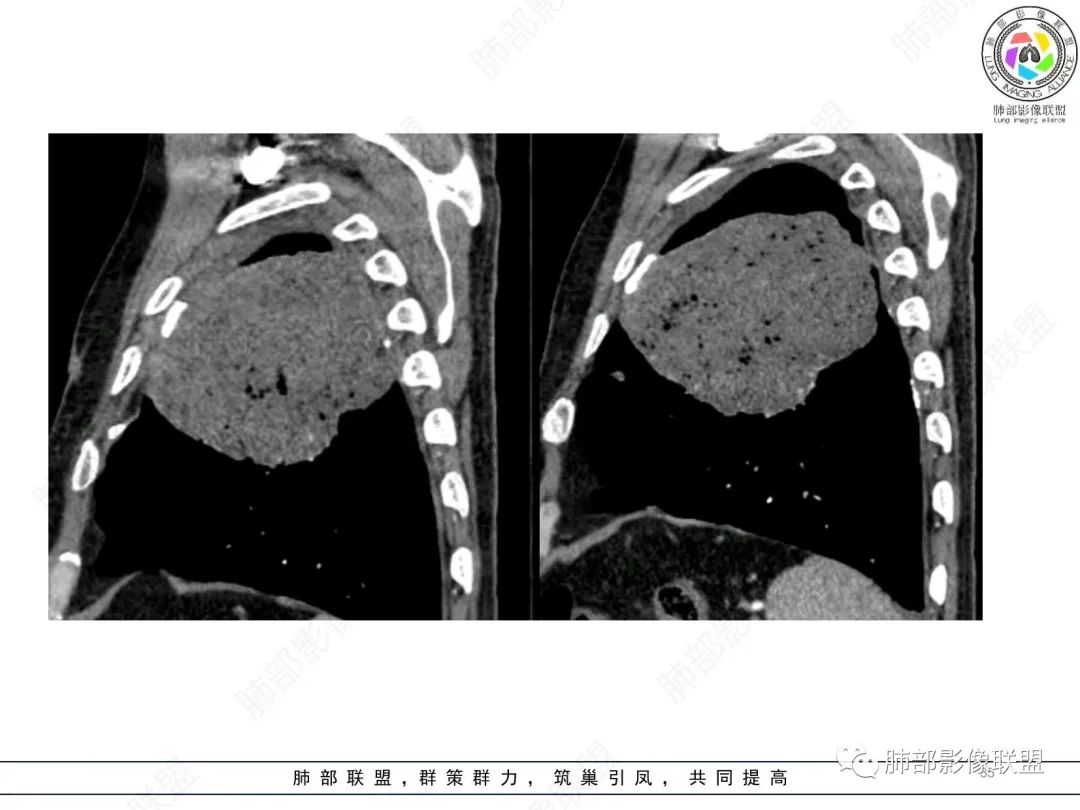

1)部位:周围型或中央型软组织肿块,以周围型为多见,且肿瘤多位于肺上叶。如本例:该肿瘤位于左肺上叶。

2)大小及形态:由于本病恶性程度高,早期症状不明显,发现时肿块均较大。如本例病变巨大。

3)肿块边界和边缘:多较清楚,呈圆形、类圆形,且由于肿块生长速度不均匀,可见分叶,毛刺少见。有报道肿块周围毛玻璃影是多形性癌特征表现。

4)密度:肿块平扫为软组织密度,由于体积较大,内部常见大片状坏死,可出现不规则厚壁空洞或坏死内多发无壁小空洞,坏死多不均匀:坏死灶内可见如柳絮样的斑片样强化灶,坏死边缘与非坏死区分界不清本例坏死较明显,密度不均匀。

5)肿瘤强化方式:肺部恶性肿瘤强化程度与其血供丰富程度相关,血供丰富多强化明显,反之则较差。由于PSC 周边实性部分富血供及内部黏液变性、坏死,增强后肿块多数呈轻-中度边缘环形强化或不均匀小斑片状强化。国外学者对照病理发现肿瘤细胞或胶原组织增强扫描时强化,无强化的低密度区代表了黏液样变性区和出血坏死区。